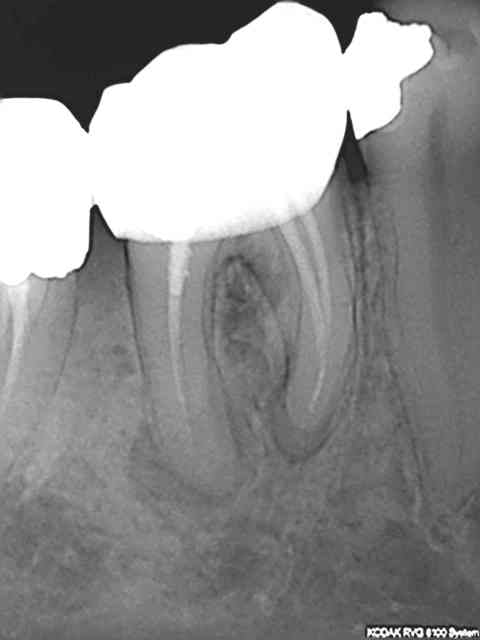

Cas quasi systématique avant de gagner sa vie dans ce pays de m.... endo à reprendre.

Séquence R25,S1,R25, S, R25, S1........ Apex.Bilan : 3 s1 à la poubelle (dé-vrillage de la pointe) 30 euros à la poubelle + 1 R25 (16 euros). Ca coute plus cher que l'aumone NGAP.